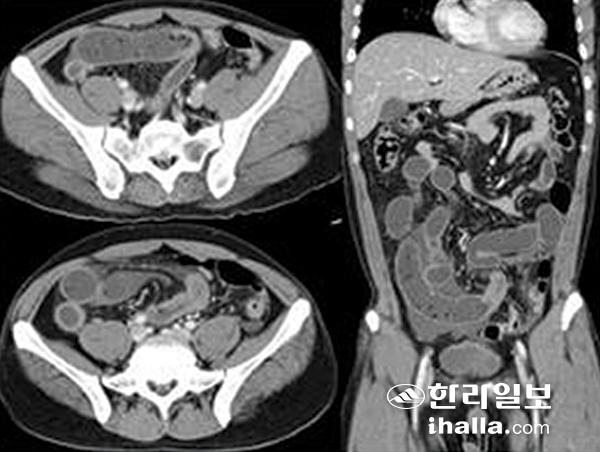

컴퓨터단층촬영상 고래회충증 소견. 전형적으로 위에 발생한 고래회충증이며, 환자는 통증 6시간 전에 생선회를 먹었고 위 전체의 부종 소견을 보인다. 사진=제주대학교병원

사진은 소장에 발생한 고래회중증의 영상 이미지. 환자는 통증 2일전 생선회를 먹었고, 원위부 소장의 협착과 근위부 소장이 확장돼 있어 장폐쇄 소견을 보인다. 사진=제주대학교병원